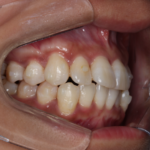

【叢生】インビザライン症例:ガタガタが気になる

治療前 治療後 症例の詳細 主訴 ガタガタが気になる ...